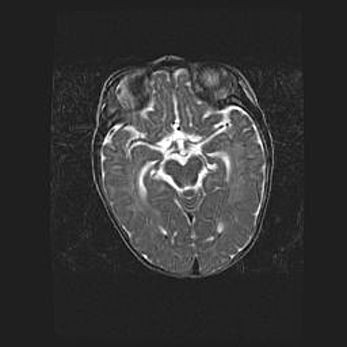

Множественные кисты обоих полушарий головного мозга, наибольшая из них в правой затылочной области. Ассиметричная атрофическая гидроцефалия.

Возраст: 7 месяцев

Вес: 5660 г

Пол: мужской

Окружность головы: 41,5 см

Срок гестации: 28-29 недель

Кисты головного мозга развиваются в результате многоочаговых некрозов вещества мозга и возникают вследствие перенесенной перинатальной инфекции, менингитов, энцефалитов, асфиксии, родовой травмы, расстройств мозгового кровообращения различного генеза. Образованию кист в веществе головного мозга плодов и новорожденных способствуют такие факторы, как высокое содержание в нем воды, недостаточная (или отсутствие) миелинизация и слабая астроглиальная реакция на повреждение.

Кисты могут сочетаться с гидроцефалией и другими поражениями головного мозга.